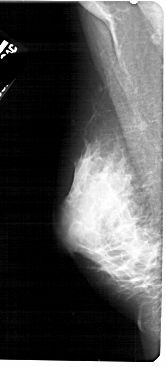

A_1746_1.LEFT_MLO

LEFT_MLO LINES 5491 PIXELS_PER_LINE 2476 BITS_PER_PIXEL 12 RESOLUTION 43.5 NON_OVERLAY